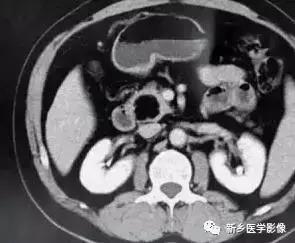

2.影像学诊断:CT 、M RI 上, 本病表现为胰腺边界清楚的大肿块, 囊实相间, 实性部分主要位于病变周边,有强化;囊性部分主要位于病灶中心区域, 囊变区密度较高, CT 值40 ~50Hu 。30 %的患者病变周边可见钙化。由于病变内常有出血,T1W I 上可见不均匀高信号, T 2WI 上见不均匀低信号 。M RCP 或E RCP 示胰管受压、移位或中断。